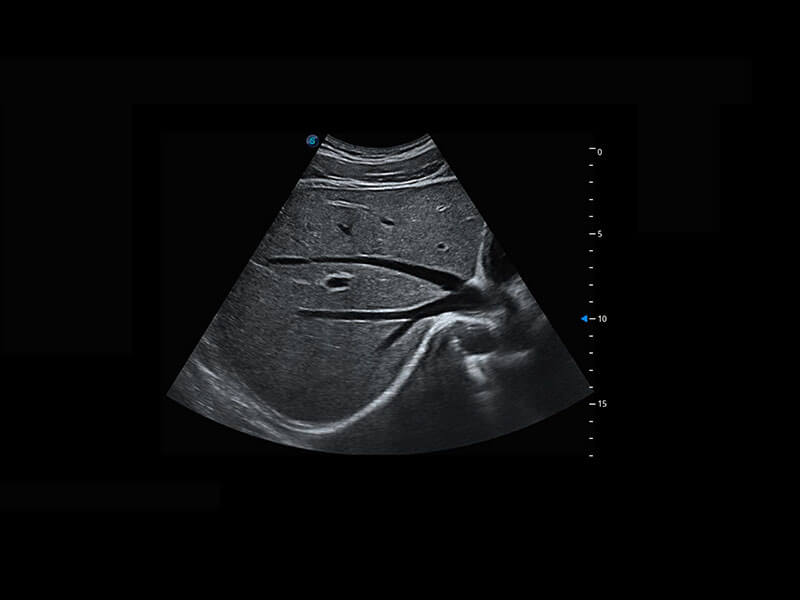

中晚孕筛查

P60提供简单易学易用的高端诊断工具,为您中晚孕筛查提供快速清晰的解剖信息。

S-Fetus能够助您在实时扫查过程中自动识别标准切面、自动测量并录入报告。一个按键,即可快速、高效地获取胎儿生理指标,简化您的产科检查操作。